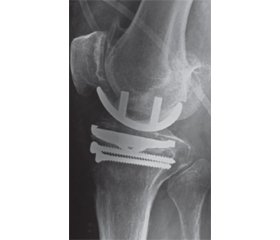

Для порівняльного аналізу результатів лікування пацієнтів зі зниженою щільністю кісткової тканини за класичною та авторською методиками були досліджені 3 групи пацієнтів. І група — 59 (67,8 %) осіб, пацієнти з нормальною щільністю кістки, яких оперували за класичною методикою монокондилярного ендопротезування; ІІ група — 6 (6,9 %) осіб, пацієнти зі зниженою щільністю кісткової тканини, яким було проведене монокондилярне ендопротезування за авторською методикою (рис. 1). Авторська методика полягає в тому, що в разі інтраопераційного виявлення зниженої щільності кісткової тканини великогомілкової кістки нами з превентивною метою проводилось установлення в сагітальній площині двох кортикальних гвинтів у великогомілкову кістку нижче від опилу плато [10]. ІІІ група — 22 (25,3 %) пацієнти зі зниженою щільністю кісткової тканини, яким виконували монокондилярне ендопротезування колінного суглоба за класичною методикою.